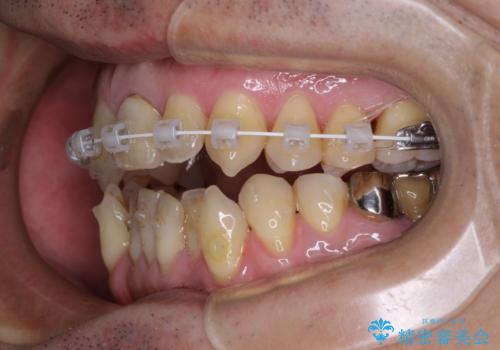

開咬の改善には、舌の突出癖改善のためにトレーニングを行いつつ、インビザラインでの矯正治療が大変有効ですが、上顎骨が下顎骨に対して前方位に位置しており、インビザライン単独で治療を行うよりは補助装置とワイヤー矯正で奥歯の咬み合わせを改善してから、開咬改善のためのインビザライン矯正治療を行うこととしました。

インビザラインを毎日22時間しっかりと装着してくださったので、我々も驚愕するほどの治療成果が達成されました。